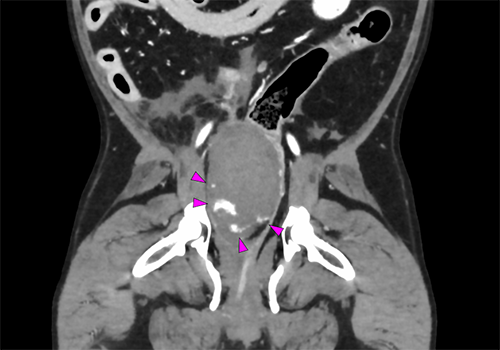

では、最後に後腹膜の血管肉腫の画像と肺転移の動画を!

ジャックラッセル・テリア 12歳

骨盤腔内/後腹膜血管肉腫